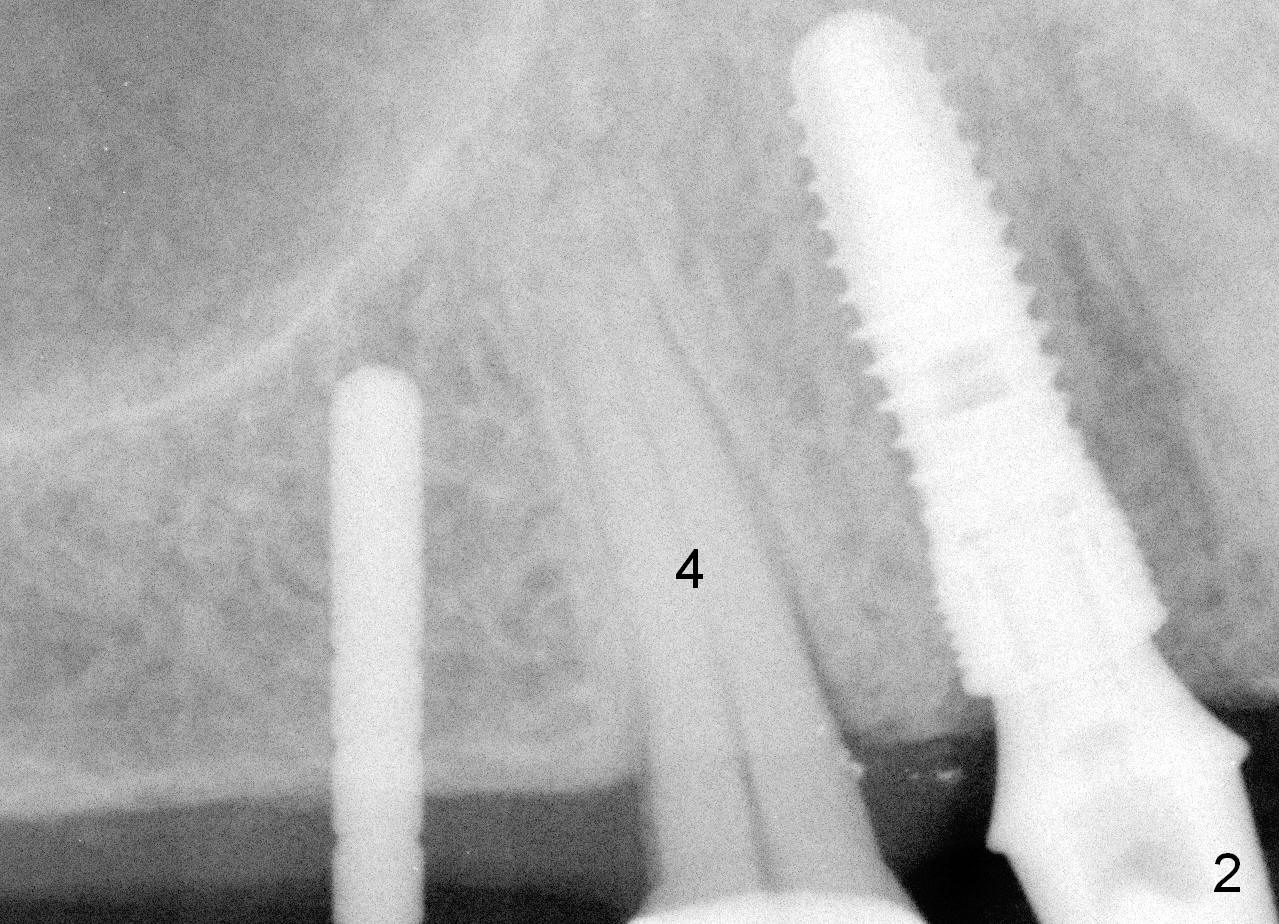

Both the teeth #30 and 31 are supraerupted. There is no restorative space for #2. So #3 implant will support the most distal crown. A 4 mm tissue punch is used, followed by a 2 mm pilot drill. Bone type is 3. A parallel pin shows that the trajectory needs to be adjusted (Fig.2). By the time a 4.5 mm tap is placed, the trajectory is within normal limit (Fig.3,4 T). A 5.3x10 mm implant is placed with insertion torque > 60 Ncm (Fig.5; *: sinus lift). After insertion of an abutment, an immediate provisional is fabricated with intention to prevent further supraeruption of the tooth #30 during #3 implant osteointegration.